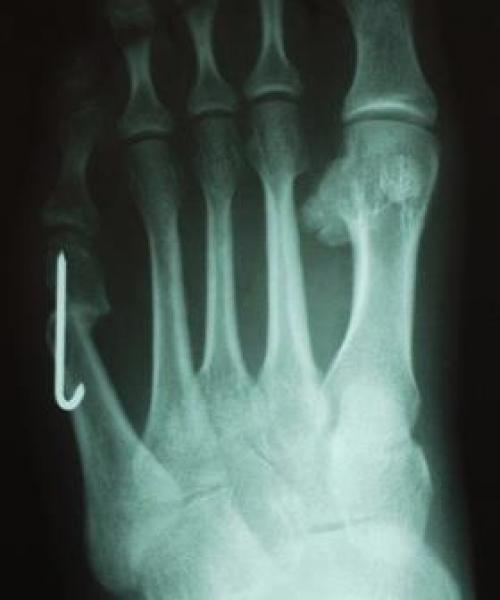

Для рентгенологической диагностики используются главным образом снимки в прямой проекции с нагрузкой. При этом оценивается 4-5 межплюсневый угол, 5 плюсне-фаланговый угол, ширина головки 5 плюсневой кости, угол наружного отклонения 5 плюсневой кости.

Используется в случаях длительно существующей деформации 1 типа, деформациях 2 и 3 типа с межплюсневым углом менее 12 °. Используются различные модификации метода. Наиболее часто применяется медиализирующая остеотомия по типу шеврон. Менее популярны поперечная остеотомия, клиновидная остеотомия с использованием пластин, остеотомии типа scarf. Фиксация фрагментов выполняется при помощи спиц Киршнера или винтов, может быть скомбинирована с наружной кондилэктомией.

Показана при деформациях 2 и 3 типа с межплюсневым углом более 12 °. Заключается в резекции подошвенной поверхности головки 5 плюсневой кости при наличии мозоли, косой остеотомии диафиза в нижней трети. Следует избегать проксимальных остеотомий в связи с плохим кровоснабжением. Фиксация выполняется при помощи 1-2 спиц или винтов.